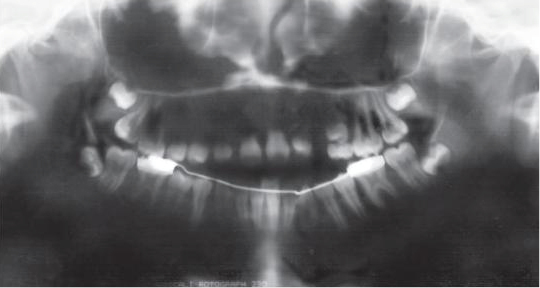

Streszczenie: Niniejsza praca kazuistyczna opisuje leczenie zaawansowanego zgryzu otwartego przedniego i bocznego z współistniejącym wrodzonym brakiem kilku zębów. U 10-letniej dziewczynki stwierdzono: otwarty kąt bródkowy, brak zwarcia warg i retruzję tkanek miękkich w punkcie pogonion, otwarty zgryz 8,5 mm, agenezję zębów siecznych górnych bocznych, bocznego oraz pierwszego zęba przedtrzonowego górnego lewego, zwężenie wymiaru poprzecznego szczęki. Zaplanowano leczenie niechirurgiczne mające na celu kontrolę wzorca pionowego, uzyskanie prawidłowego nagryzu pionowego i zamknięcie luk w górnym łuku zębowym, aby zapewnić zadowalającą okluzję oraz estetykę twarzy i zębów.